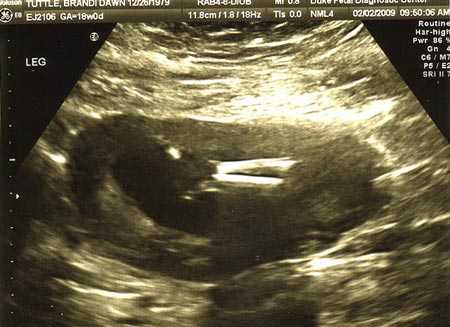

УЗИ плода на 18 неделе беременности

Примерно в этот же период беременная идет на ультразвуковое исследование. Данный метод с использованием современного аппарата позволяет сделать фото живота на 18 неделе беременности и определить, в норме ли параметры развития ребенка. УЗИ помогает выявить множество патологий. К примеру, синдром Дауна, пороки сердца, маловодие или неправильное предлежание плаценты. К тому же врач посмотрит, соответствует ли внутриутробное развитие сроку беременности: делает замеры частей тела, уточняет, сформированы ли внутренние органы.

Ультразвуковое исследование ( УЗИ ) на 18 неделе беременности

Между 18 и 22 неделями женщина должна пройти повторное УЗИ.

На 18 неделе вы уже сможете точно узнать, кто у вас родится: сын или дочка. Кроме того, во время исследования врач сможет определить, нет ли у малыша каких-либо пороков развития, например, синдрома Дауна или Патау. Также можно выявить пороки развития сердца малыша.

Во время УЗИ обязательно исследуется состояние плаценты: это позволяет спрогнозировать дальнейшее течение беременности.

Фото УЗИ на 18 неделе беременности

УЗИ в 18 недель

18 неделя беременности фото УЗИ